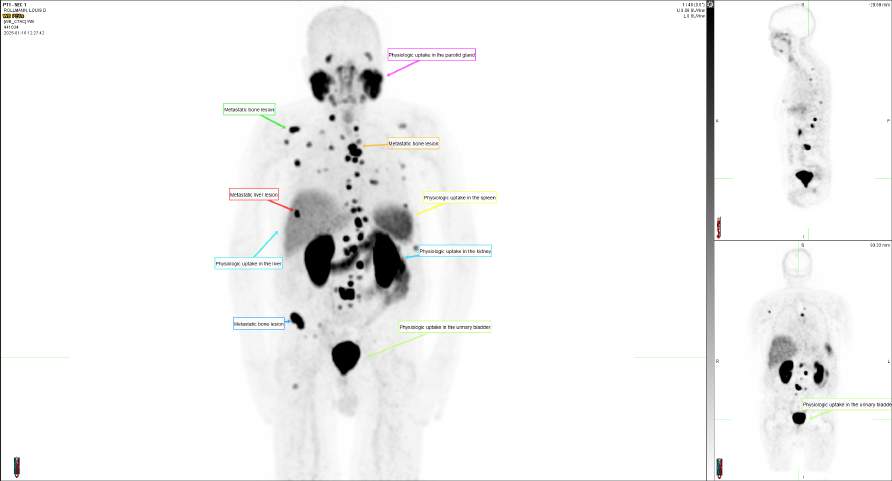

prompted a PSMA PET scan, which revealed metastases to the left posterior iliac bone and rib. These sites were treated with stereotactic body radiation therapy (SBRT).

He received antiresorptive therapy (Xgeva) and multiple courses of androgen deprivation therapy (Leuprolide, Casodex, Xtandi). However, three years later, the disease progressed again, as evidenced by di use osseous activity on PSMA PET imaging.

Advanced Targeted Therapy: Pluvicto (Lutetium-177 PSMA) Given his progressive, androgen-independent disease, the patient was referred for Pluvicto therapy. Following the rst dose, a notable drop in PSA was observed within four weeks, suggesting early biochemical response. A follow-up PSMA PET scan is scheduled to assess imaging-based response.